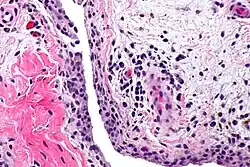

Chronic synovitis

Synovitis may occur in association with arthritis as well as lupus, gout, and other conditions. Synovitis is more commonly found in rheumatoid arthritis than in other forms of arthritis, and can thus serve as a distinguishing factor, although it is also present in many joints affected with osteoarthritis.[1][2] In rheumatoid arthritis, the fibroblast-like synoviocytes, highly specialized mesenchymal cells found in the synovial membrane, play an active and prominent role in the synovitis.[3] Long term occurrence of synovitis can result in degeneration of the joint.